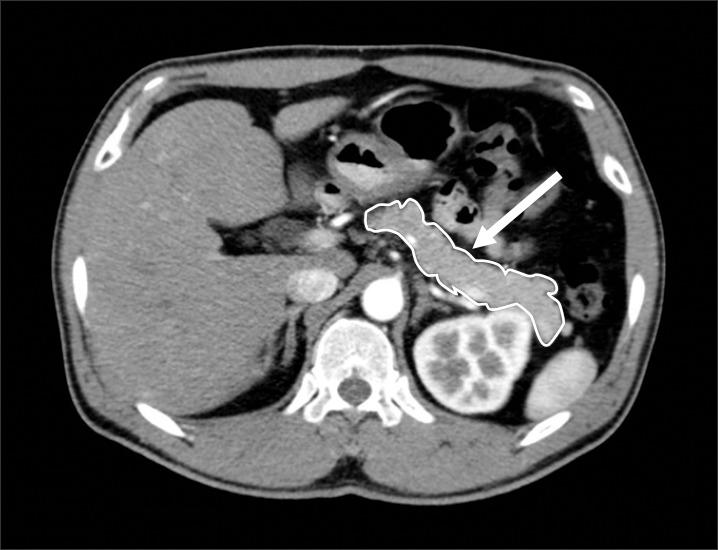

We retrospectively reviewed the cases of 26 patients who could be compared in abdominal computed tomography before and after distal pancreatectomy for benign or malignant lesions between January, 1999 to June, 2010.

我们回顾性分析了1999年1月至2010年6月期间因良性或恶性病变接受胰体尾切除术的26例患者的病例,这些患者在术前和术后均进行了腹部计算机断层扫描,以便进行对比。